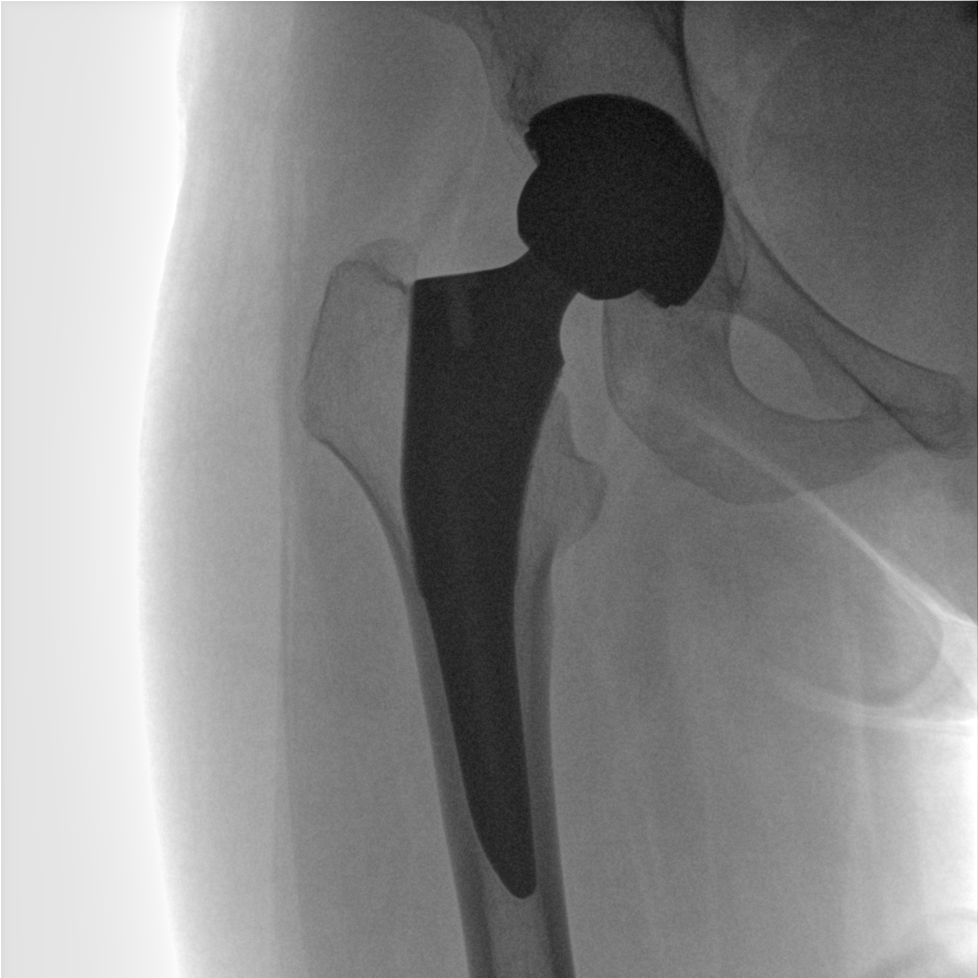

術(shù)中三維成像和橫斷面圖像提供多角度的手術(shù)診斷信息,輔助醫(yī)生進(jìn)行術(shù)中評(píng)估判斷,諸如骨折復(fù)位情況和內(nèi)植入螺釘?shù)某叽绾臀恢?,輔助手術(shù)更好地完成。

提供更大的術(shù)中三維成像視野,采集更多圖像信息,可一次拍全全段頸椎、全段腰椎、七節(jié)胸椎、雙側(cè)骶髂關(guān)節(jié)、股骨頭及單側(cè)盆骨。